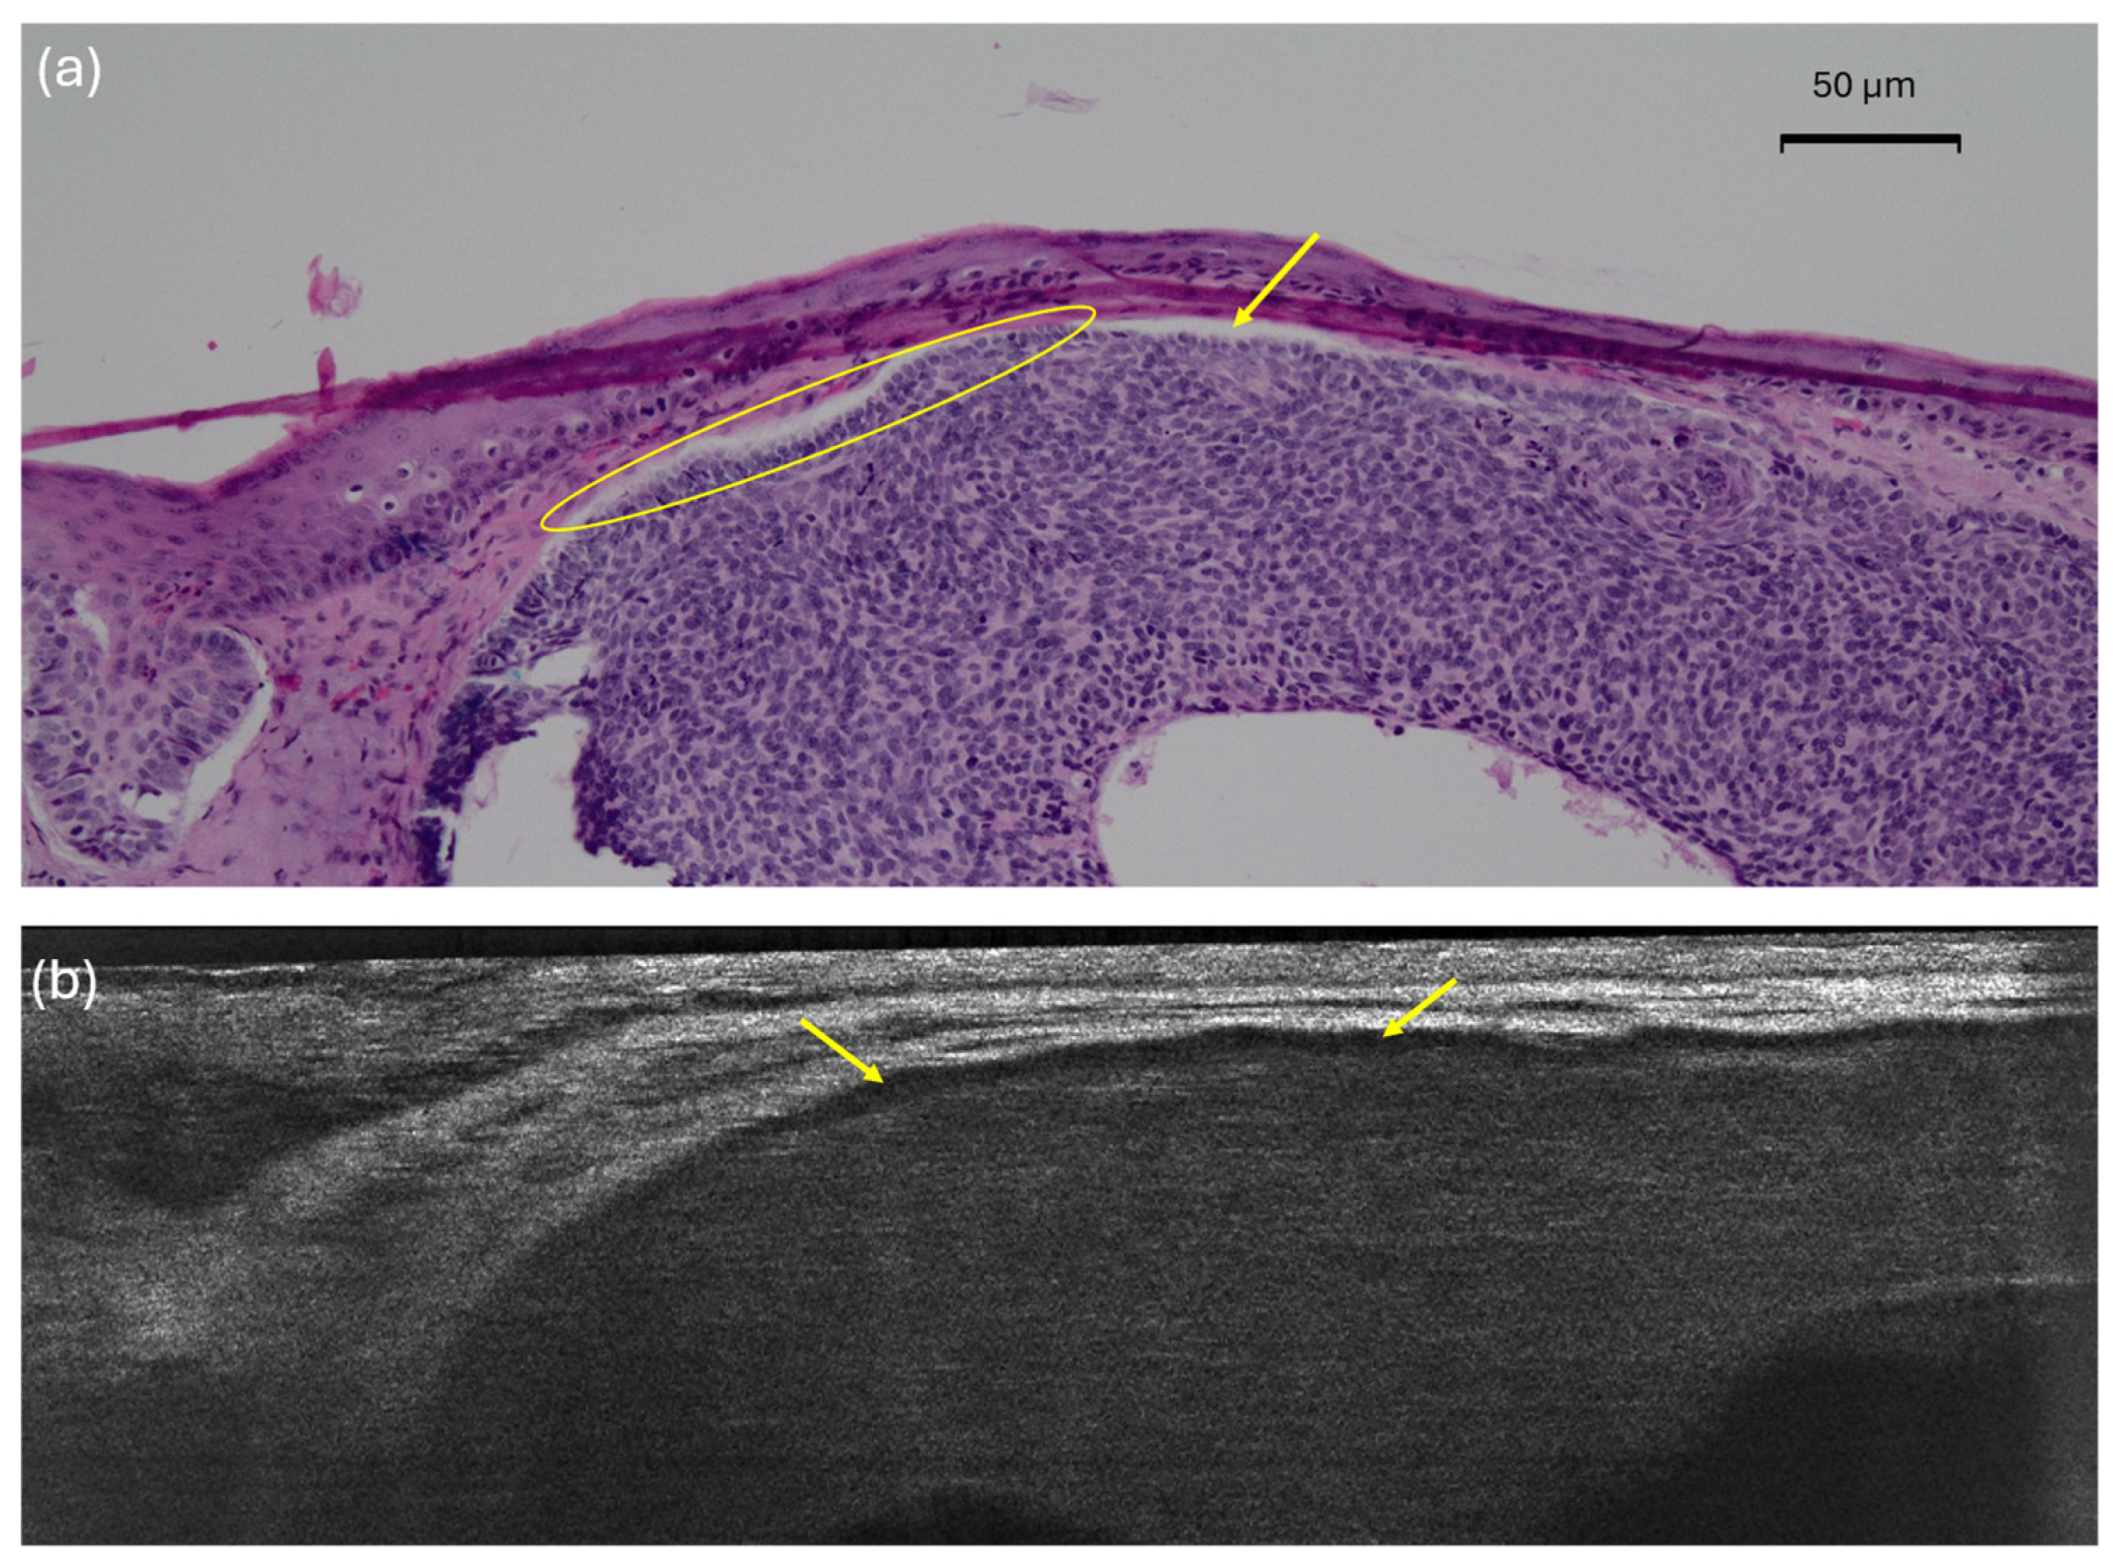

| Disrupted dermal-epidermal junction | Loss of a clear separation between the epidermis and the dermis. It may be related to the presence of hemispheric lobules leaning towards the epidermis, ulceration, or crusts | Loss of a clear separation between the epidermis and the dermis. It may be related to the presence of hemispheric lobules leaning towards the epidermis, ulceration, or crusts |